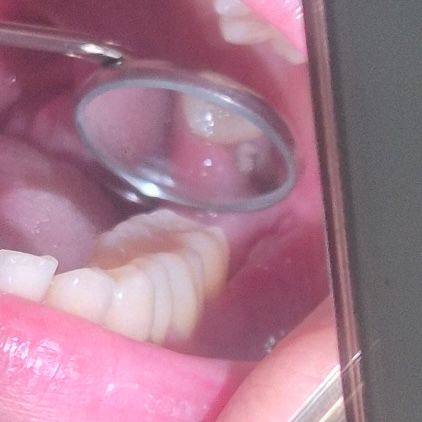

사랑니 발치 후 구멍에 하얀색으로 먼가가 보입니다 갠찮은걸까요?ㅠㅠ

사랑니 발치 후 8일차입니다. 통증이 계속 심해서 항생제와 진통제 꾸준히 복용중이예요! 오늘 사랑니 발치한 구멍을 보니 하얀색으로 먼가가 보이는데 괜찮은 걸까요ㅠㅠ

• 1번 째 사진

사진으로 볼 때는 사랑니를 발치한 부위에 조직이 차오르거나 이물질이 끼어 들어간 것으로 보입니다. 크게 문제가 되지 않을 것으로 생각되나 걱정이 되신다. 치과에서 진료를 받아보는 것을 권유드립니다.

사랑니 발치 한 곳에 살이 차오르면서 하얗게 보이는 것이 정상적인 반응입니다. 괜찮습니다.

사랑니 발치를 하고나서 치유되는과정중에 자연스러운 현상입니다. 너무 걱정하지 않으셔도 될것같습니다.

발치 후, 상처가 치유되는 과정에서 하얀색으로 보이는 조직 형성될수 있습니다. 정상적으로 회복되는 과정이기에 걱정하지 않으셔도 됩니다.